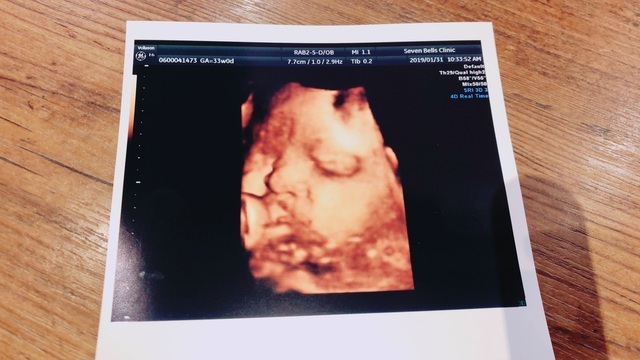

エコー写真撮影時のエピソード:

お顔がはっきり見えていることです!里帰り先の産婦人科では、4Dのエコー写真を毎回撮ってもらえる婦人科で、初めて4Dのエコー写真を見せて貰ったときの一枚です。普通のエコー写真ではわからない表情まで確認でき、こんなにしっかり育っているんだなーと感動しました!